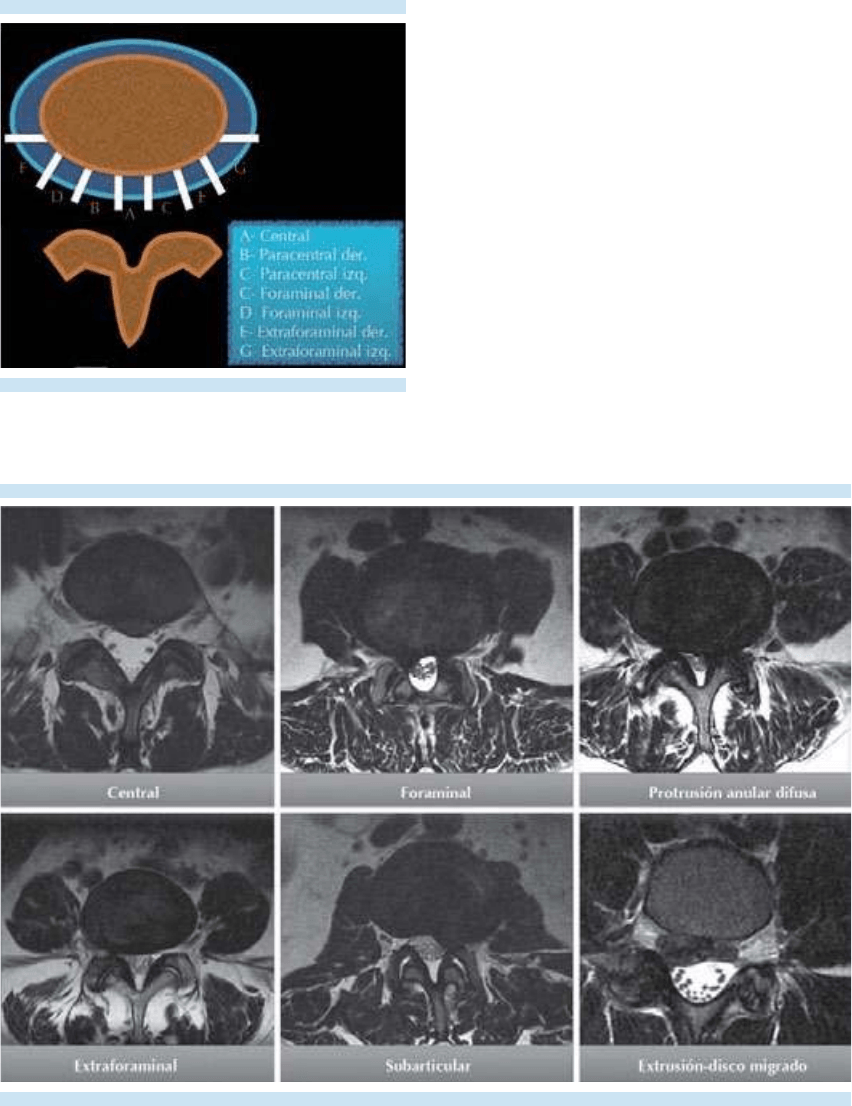

3. Evaluación del disco intervertebral.

4. Evaluación de las articulaciones face-

tarias, láminas, pedículos, procesos

transversos y espinosos; del canal central

y los recesos laterales.